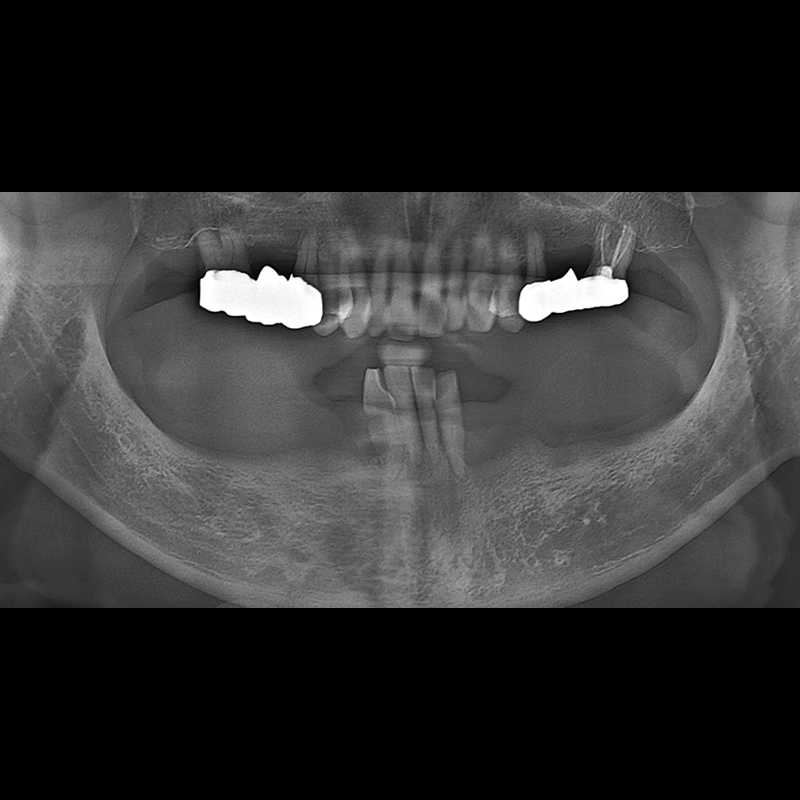

BEFORE AFTER

임플란트 전후사진 2025.05.30

결손된 치아 부분과 살리기 힘든 치아 위치에 임플란트를 식립하였습니다.